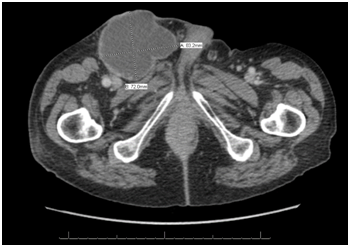

CT of the chest, abdomen and pelvis was then performed in order to determine the extent of the disease. Imaging revealed a large necrotic right inguinal lymph node (Figure 2). There was also evidence of involvement of the contralateral inguinal lymph nodes. Needle aspiration of the lymph node mass confirmed metastatic spread from the scrotal SCC.

Figure 2 Large necrotic right inguinal lymph node seen on axial CT image.